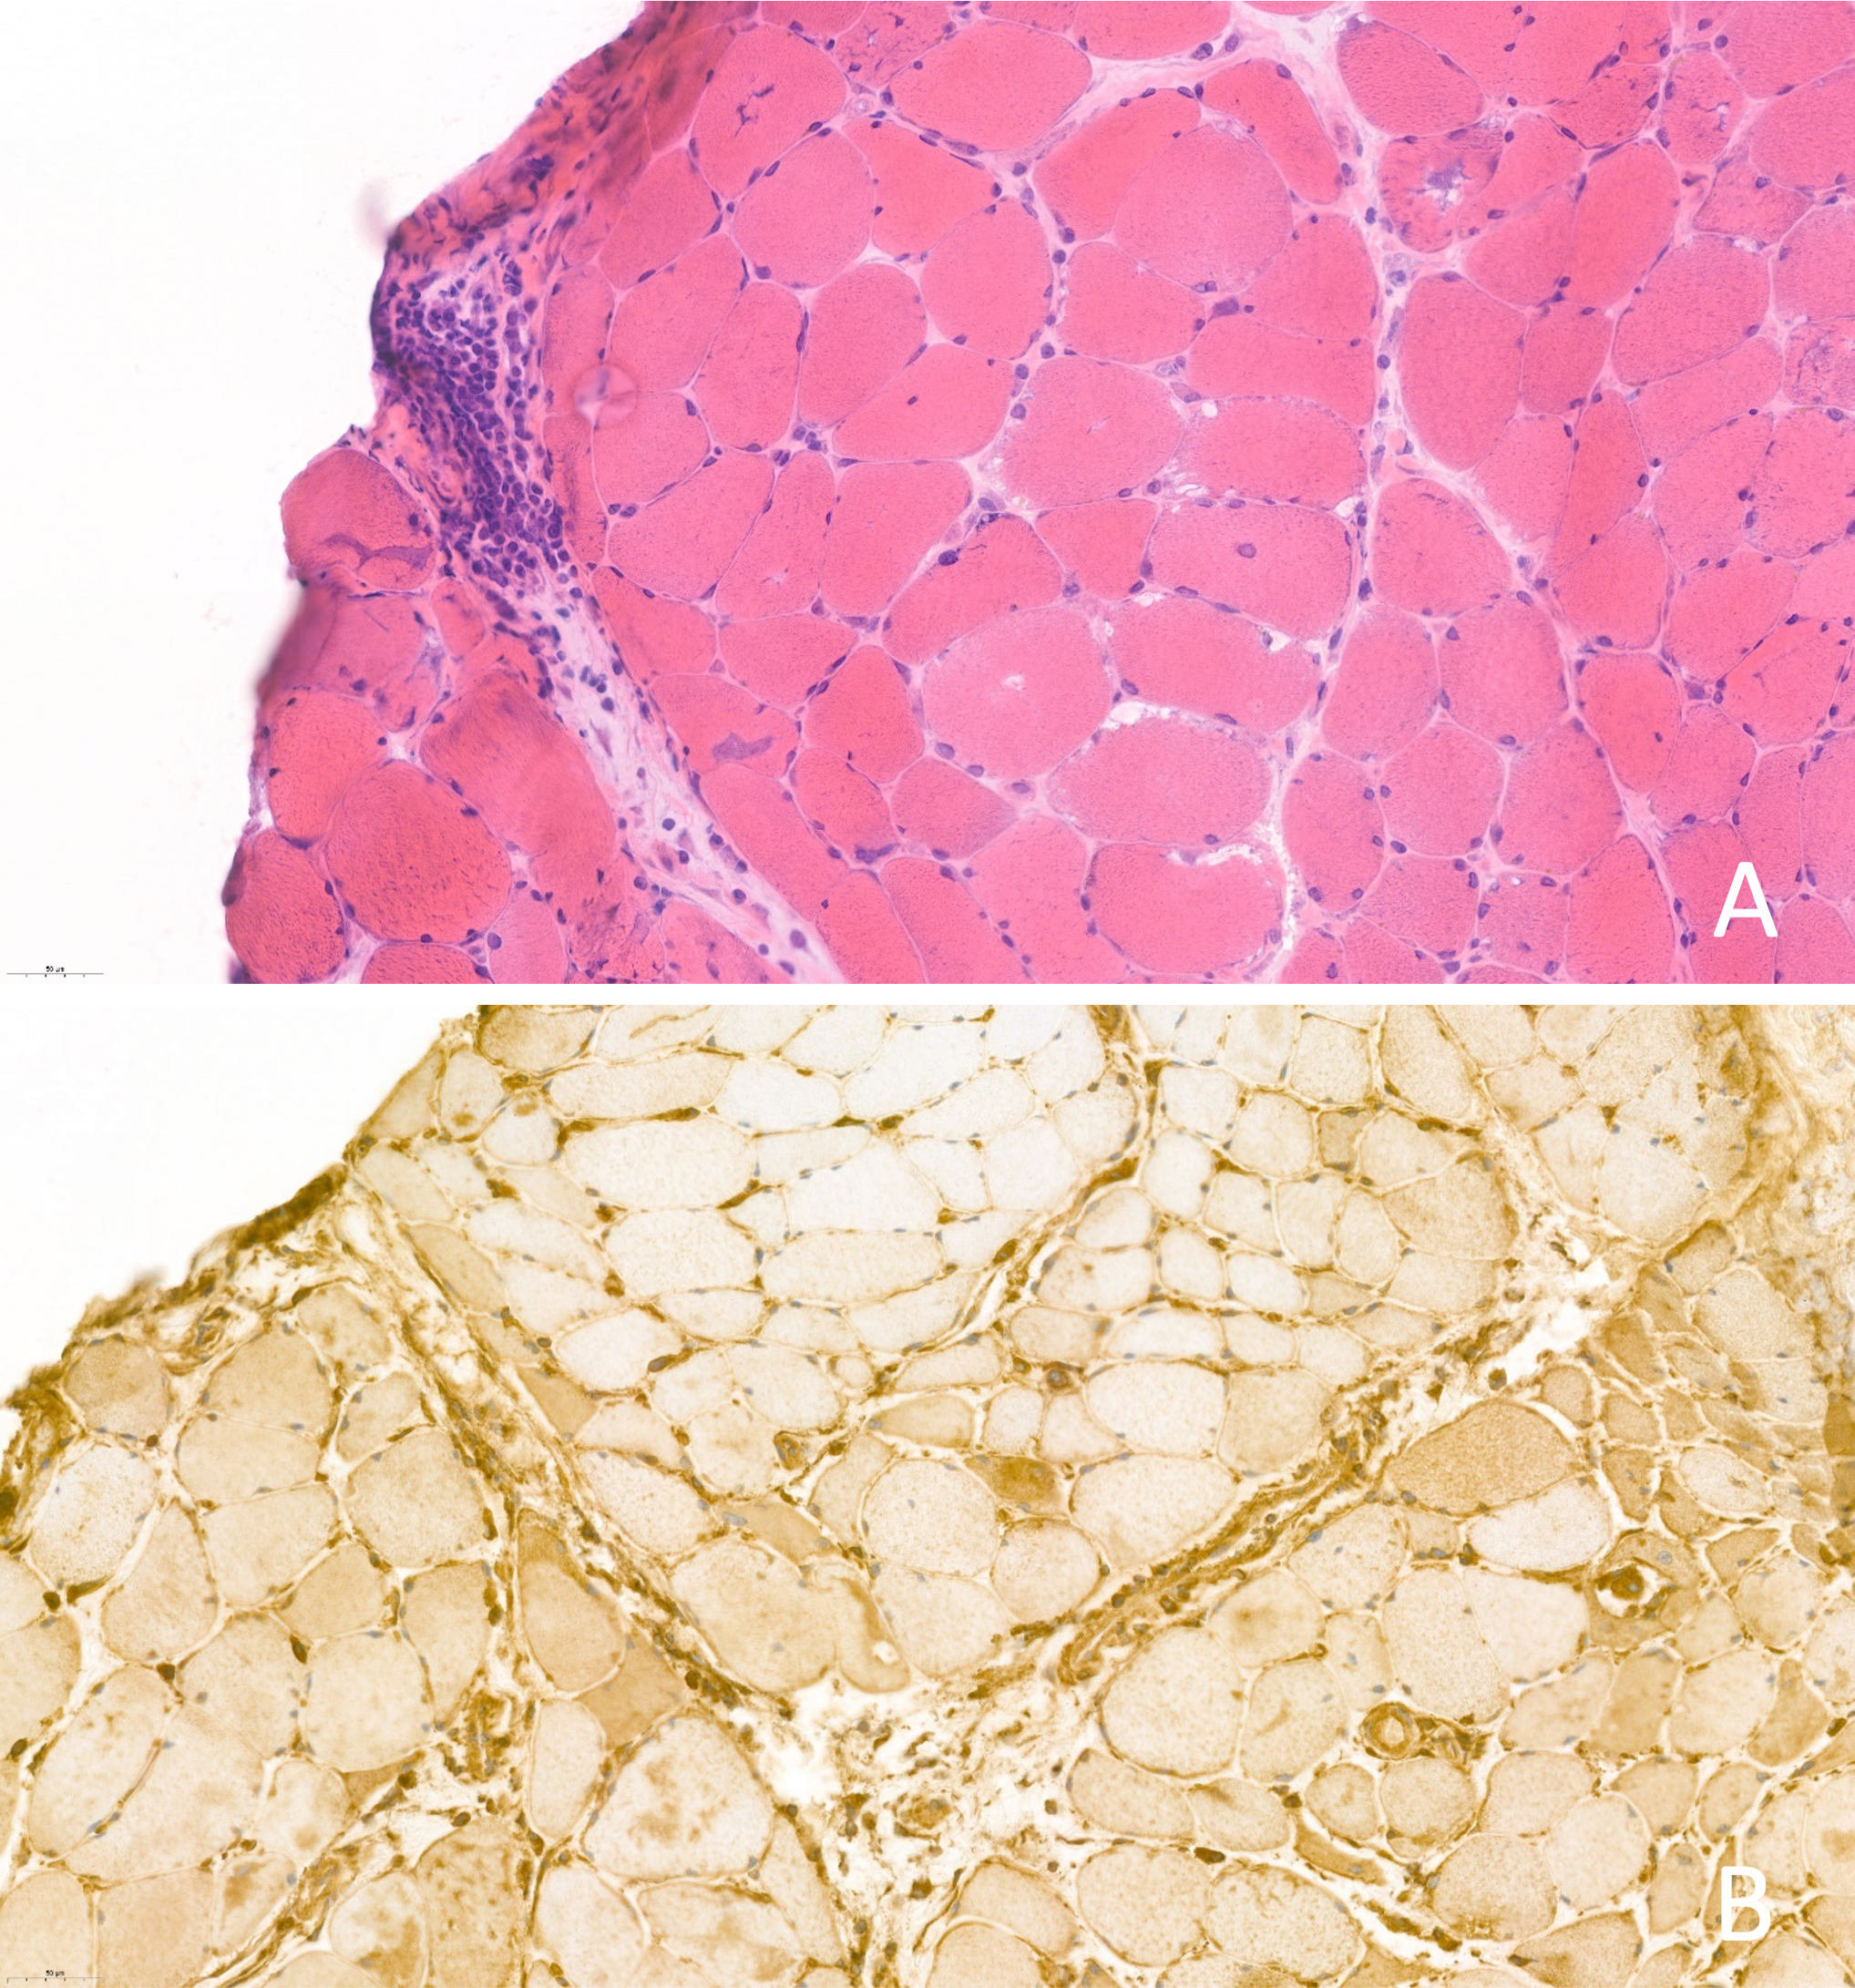

Figure 2

(A) Hematoxylin-eosin staining 40x. Muscle biopsy with perifascicular atrophy and inflammatory cells; (B) MHC class I immunostaining 40x.

A 75-year-old patient with a history of locally advanced high-grade urothelial carcinoma underwent radical cystectomy, lymphadenectomy, and Bricker-type cutaneous ureteral ileostomy in December 2020, not considering himself a candidate for adjuvant treatment with platinum in a context given a history of severe hearing loss and peripheral claudication. Due to dysphagia to solids and liquids, erythematous-violaceous lesions in the joints (Figure 1), pain in the upper extremities and proximal and symmetric weakness of the upper extremities with a CK elevation >500 and significant underlying functional limitation of a month and a half evolution, he was admitted for study in November 2021 with a diagnosis of probable dermatomyositis under study. Treatment with bolus corticosteroids was started on admission, escalating treatment to gamma globulins and methotrexate, given the clinical severity. During hospital admission, electromyography and magnetic resonance imaging were performed with findings compatible with diffuse myopathy and inflammatory signs and confirmatory muscle biopsy (Figure 2) with weak anti-TIF-1γ positivity, suggesting a paraneoplastic etiology. A PET-CT confirmed hypermetabolic 7mm adenopathy in the right internal iliac chain, suspicious of tumor recurrence. Chemo-radiotherapy treatment 30.6Gy was started in 34 concurrent sessions with weekly carboplatin during January and February 2021 with a complete response. After completing the treatment with chemo-radiotherapy, the patient presented a favorable evolution of the debut symptoms, with a complete resolution of muscle weakness and dysphagia after a few months.